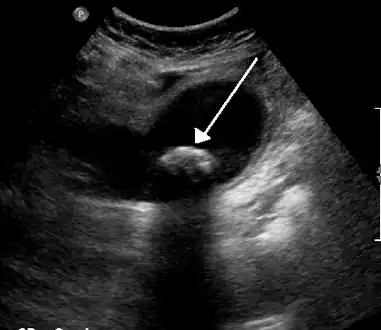

On abdominal ultrasound, sinking gallstones usually have posterior acoustic shadowing. In floating gallstones, reverberation echoes (or comet-tail artifact) is seen instead in a clinical condition called adenomyomatosis. Another sign is wall-echo-shadow (WES) triad (or double-arc shadow) which is also characteristic of gallstones.[40]

- A 1.9 cm gallstone impacted in the neck of the gallbladder and leading to cholecystitis as seen on ultrasound. There is 4 mm gall bladder wall thickening.

Biliary sludge and gallstones. There is borderline thickening of the gallbladder wall.- Gallstones as seen on plain X-ray